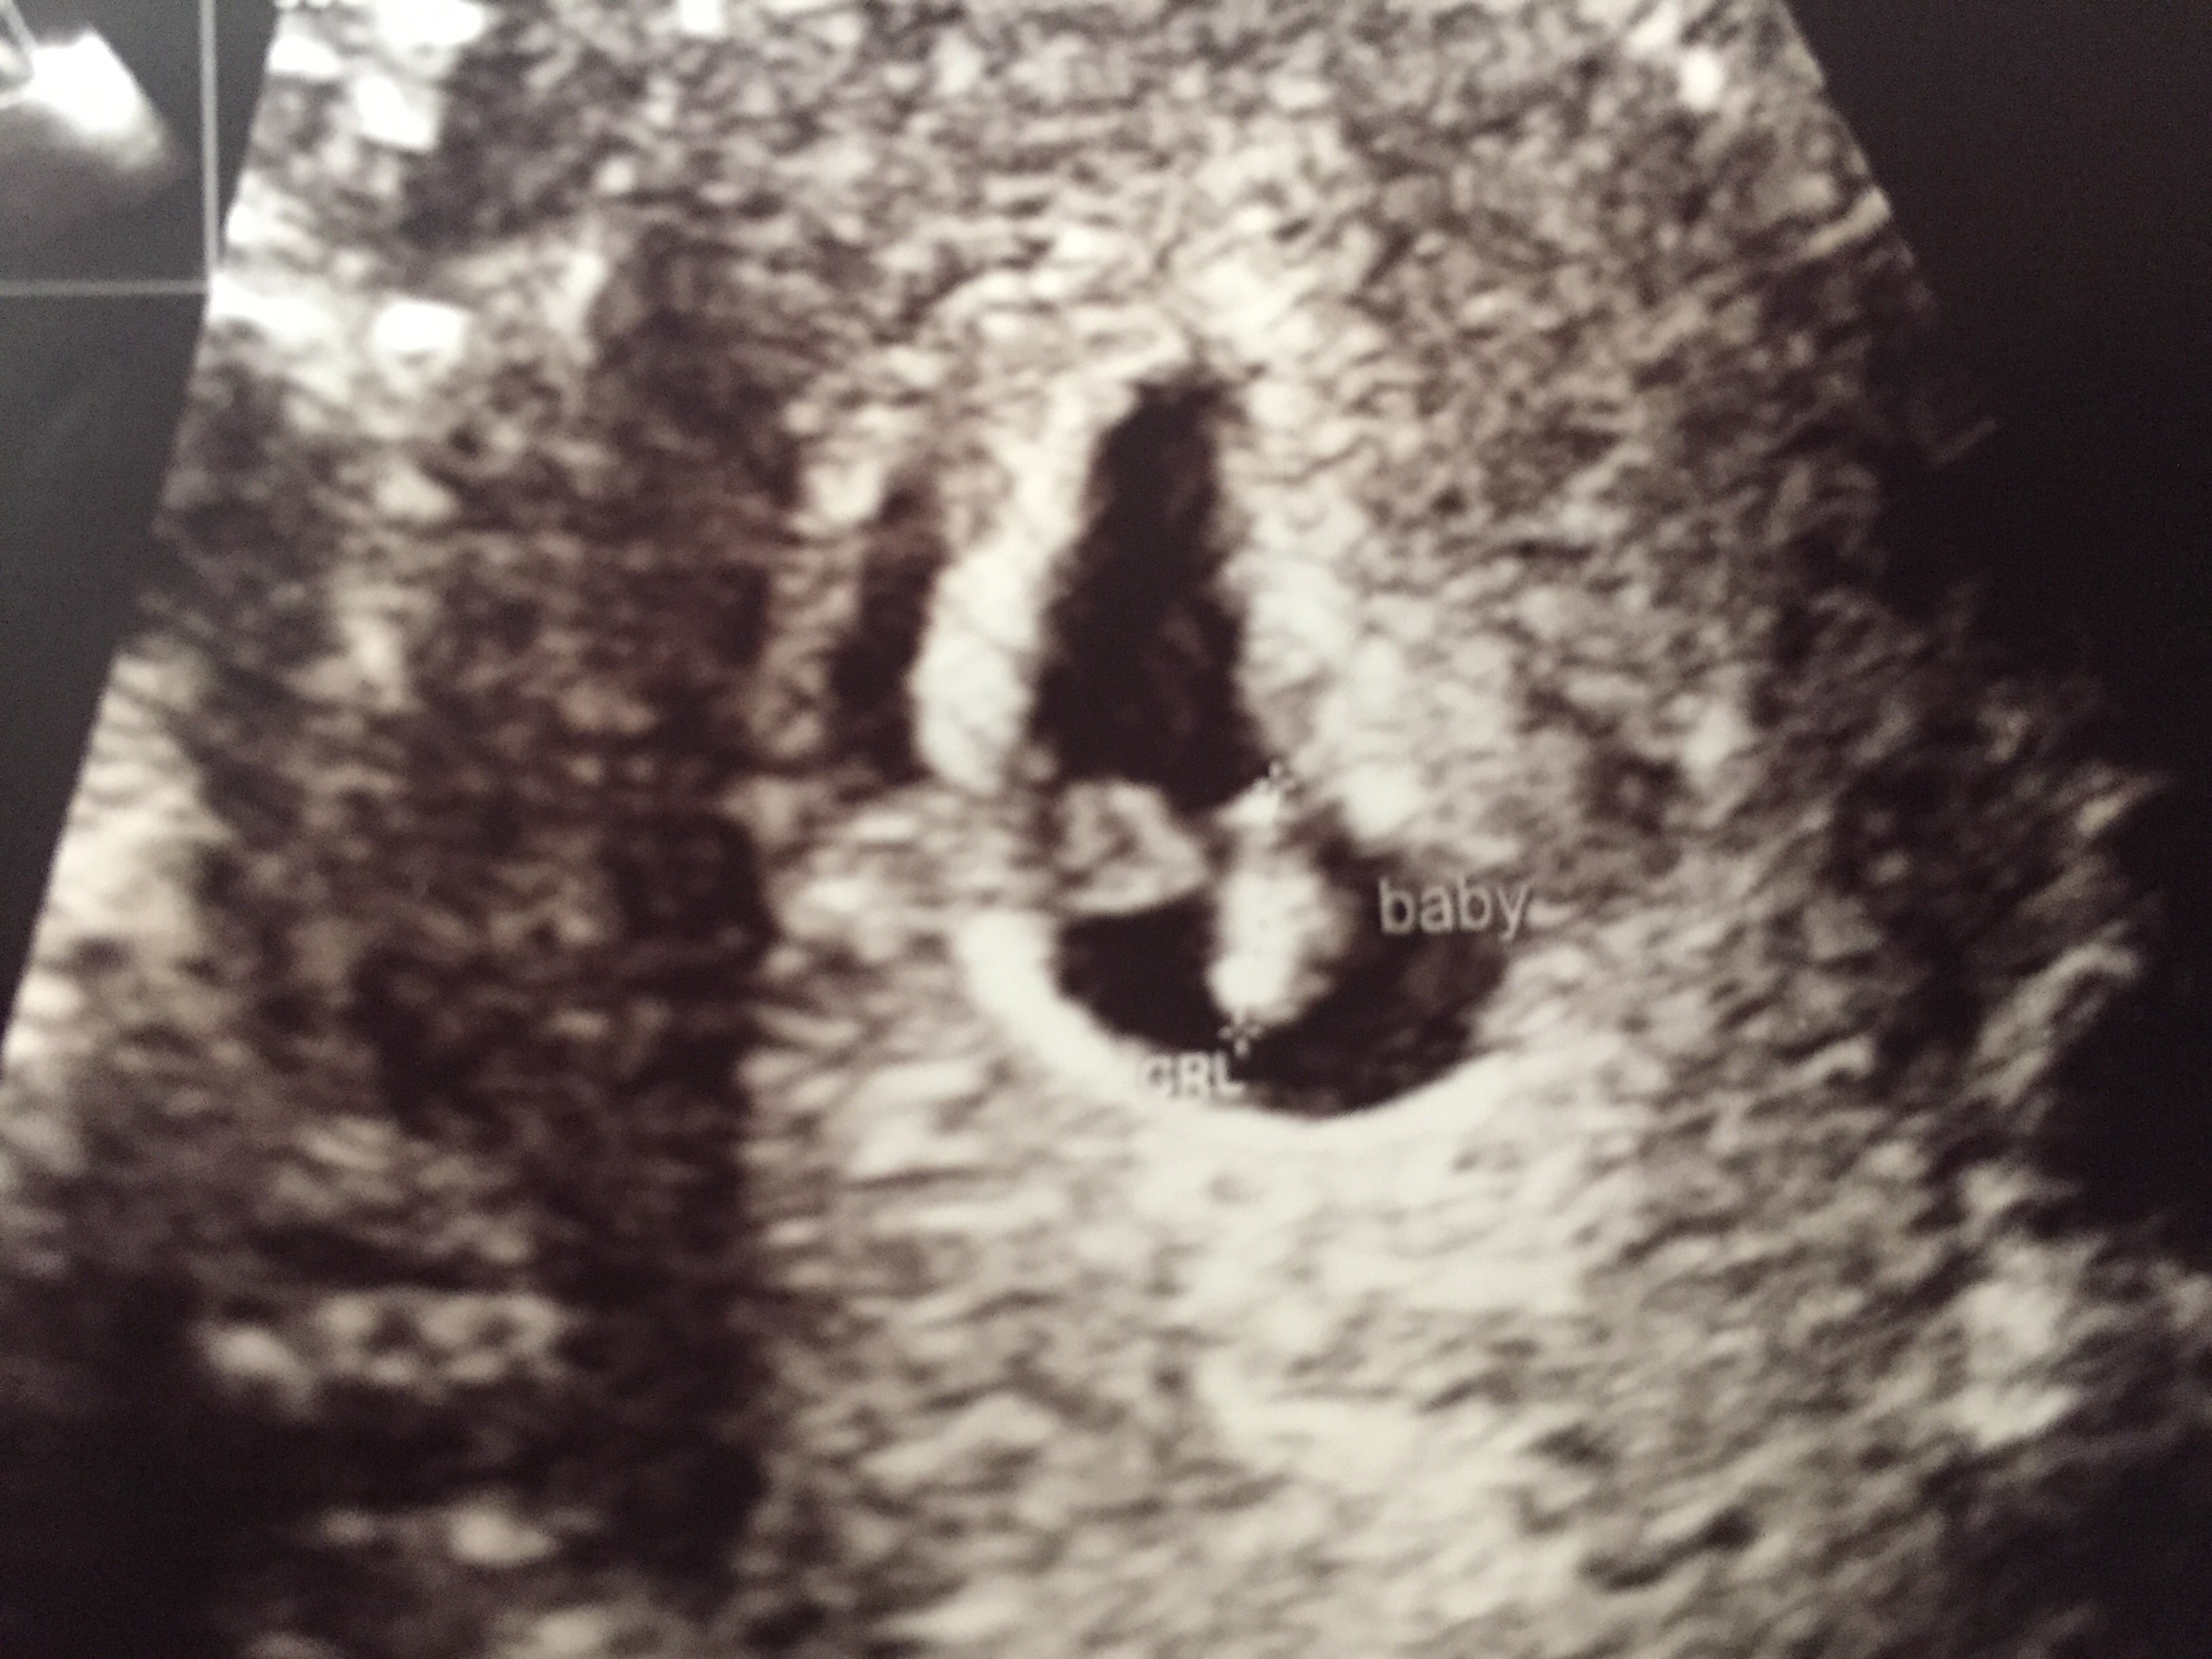

Is it just me, or do you see a litle human form in there to

ETA: HR 130